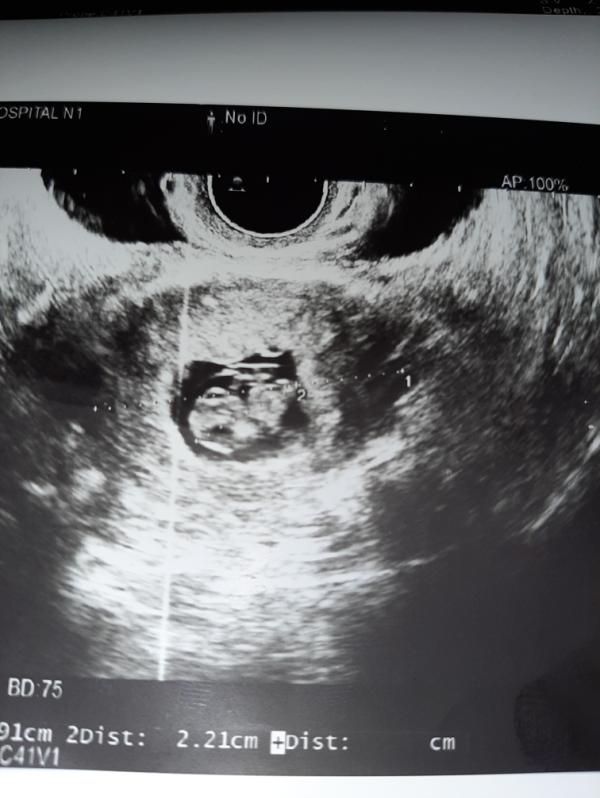

Первое фото нашей крохи😘 с малышом все нормально. Гипертонус по задней стенке. Узист мне сказала что есть гимотома.но в заключении не написала о гимотоме почему-то 🤷♀️ половой, физический психо-эмоциональный покой. Папарверин и тренакса. Шейка закрыта. Спасибо девочки всем за поддержку и советы 😘